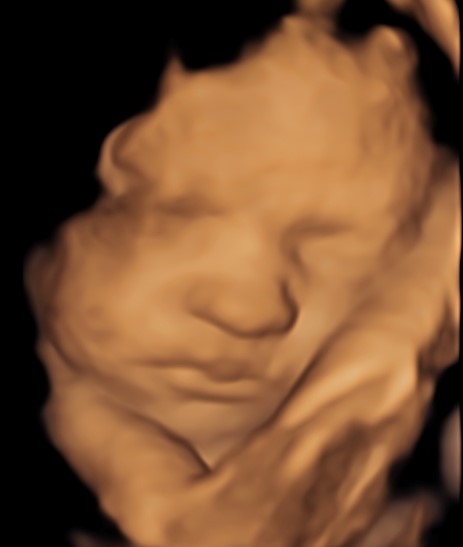

Monmouth County’s First 4D/5D/HD Live Ultrasound Studio

4D/5D/HD Ultrasound Gallery